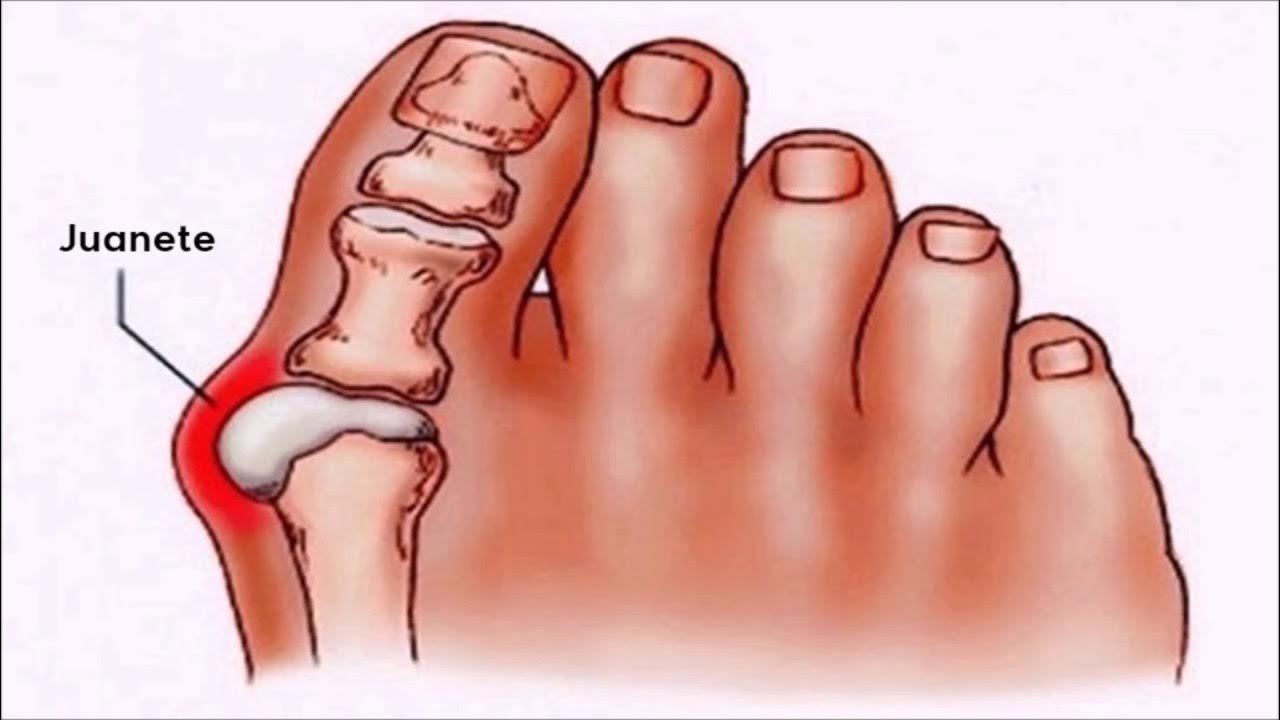

Симптомы и лечение остеоартроза узелков Гебердена: фотогалерея